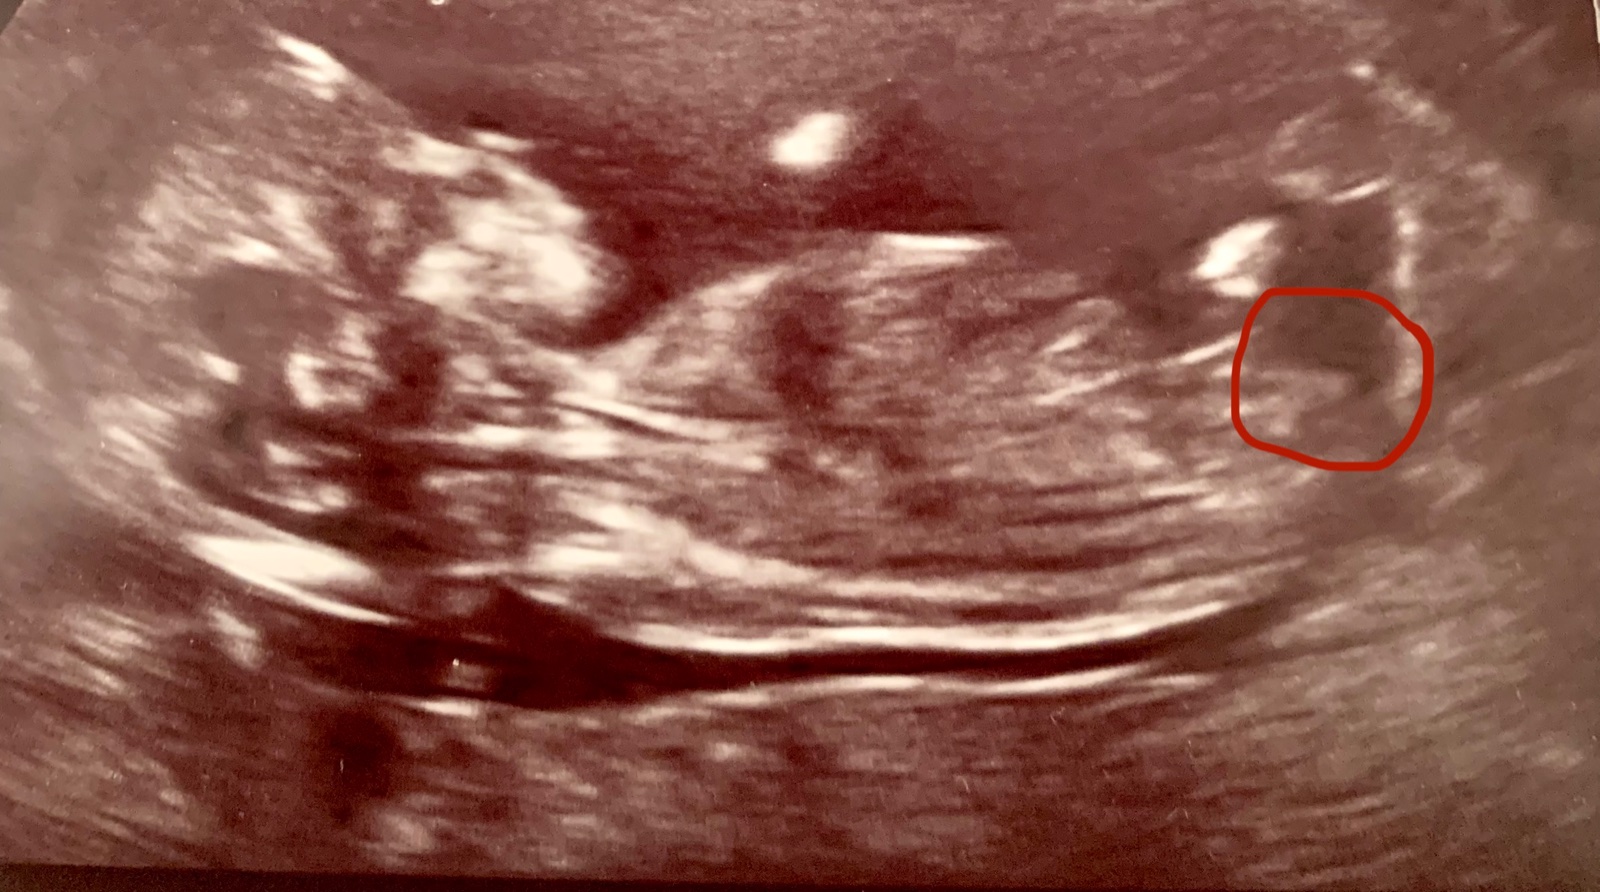

chtěla bych se vás zeptat, jestli to, co je označené na fotce ultrazvuku je “pohlavní hrbolek”, podle kterého se dá poznat pohlaví.

z Vaší fotografie to lze těžko říci, rovina řezu není ideální. Většinou jedna fotografie nedokáže nahradit vyšetření naživo a obtížně se k tomu přesněji vyjadřuje ☹